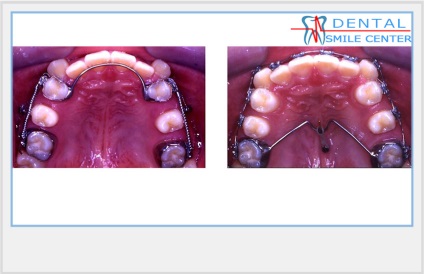

A szájüregi distaliziruschie apprat. Sok eszközök distalization zápfog. Készülékek ritkábban használtak, például a korlátozott hely a nyelvet. Nyelv nem tudja ellátni teljes funkcióját.

A fenti eszközök vannak kitéve szegmentális aktiválási, 1 alkalommal havonta. Azaz, 1 alkalommal havonta aktiváljuk az egyik oldalon, a második alkalommal - a második oldalon.